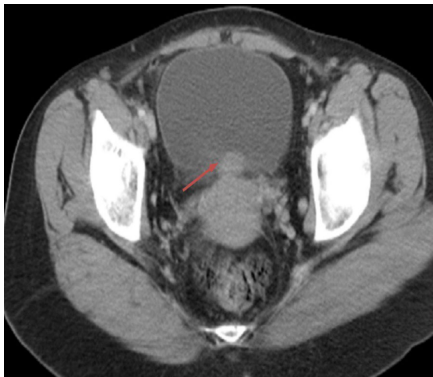

研究团队采用了循序渐进的诊断策略:首先通过实验室检查排除常见泌尿系统疾病,发现患者存在明显血尿(显微镜下满视野红细胞)和国际标准化比值(INR)2.5的凝血异常。影像学检查成为关键突破口,超声(US)初步发现膀胱后壁占位,计算机断层扫描(CT)精确定位到一个3cm的肿块,磁共振成像(MRI)则进一步显示病灶在T2加权像上的特征性低信号表现。尽管膀胱镜(Cystopanendoscopy, CPE)和诊断性腹腔镜可能提供更多信息,但基于影像学的高度特异性表现,团队决定直接进行手术治疗。

Differential diagnosis, investigations, and treatment部分展现了临床思维过程。影像学检查的价值在此得到充分体现:CT清晰显示了膀胱后壁3cm占位及其与子宫的解剖关系